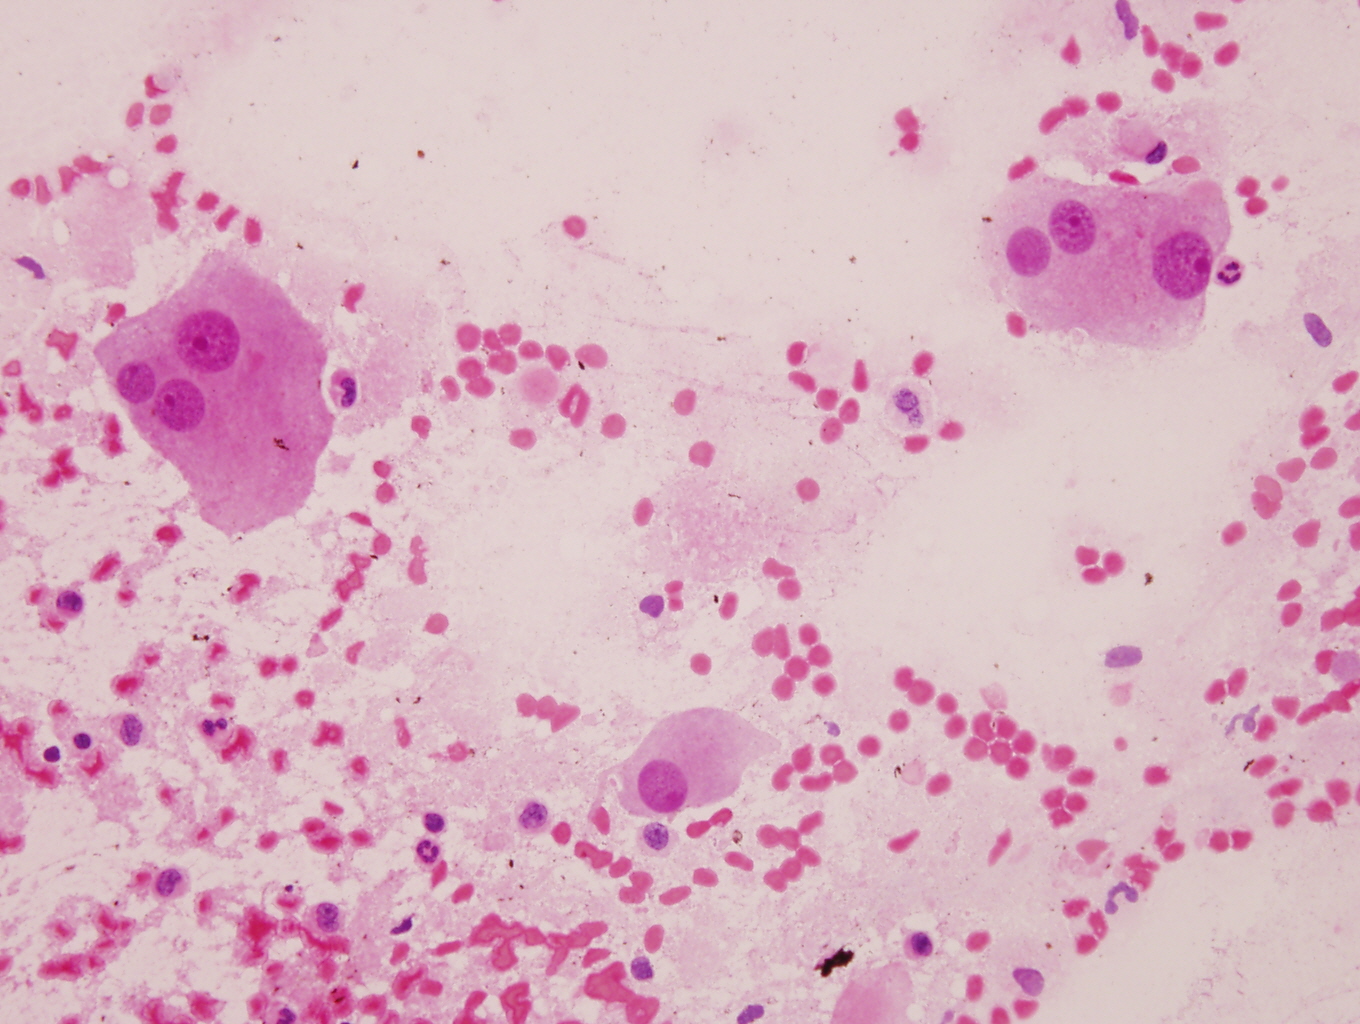

Cytology description

- Ganglion cells: larger cells, abundant cytoplasm, fine chromatin, prominent nucleoli

- Neuroblasts: uniform, small, blue cells with scant, eosinophilic, fibrillary cytoplasm; hyperchromatic to vesicular chromatin

- May form Homer Wright pseudorosettes

Cytology images